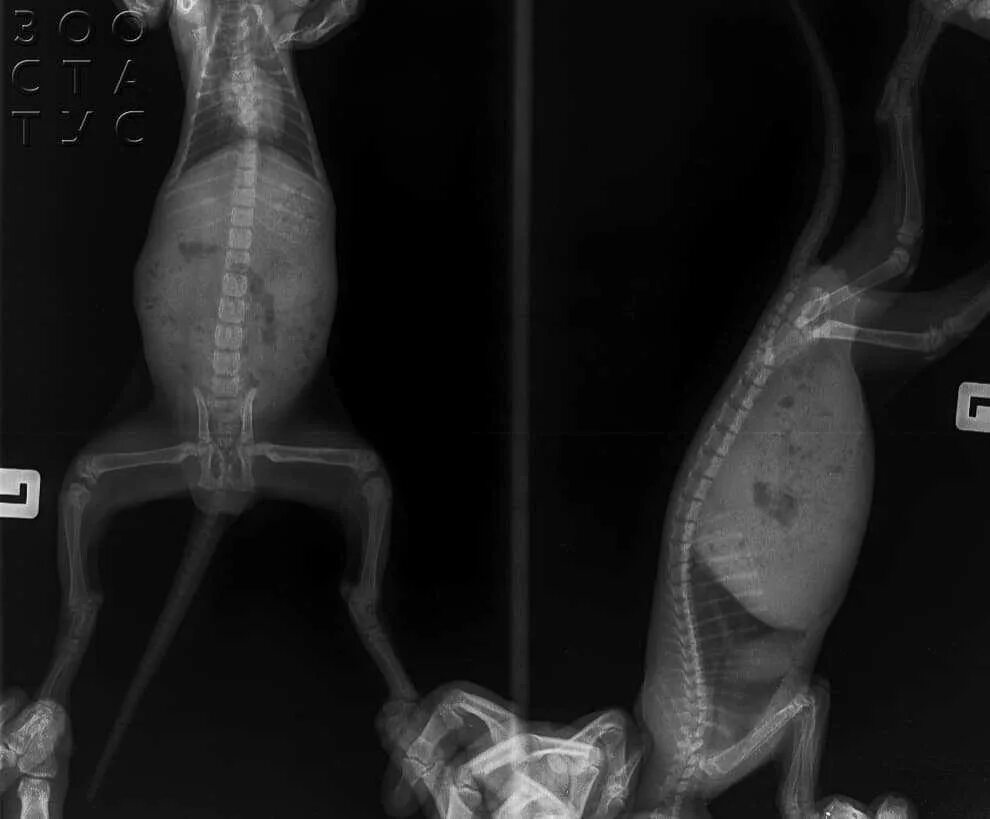

Рахит у животных